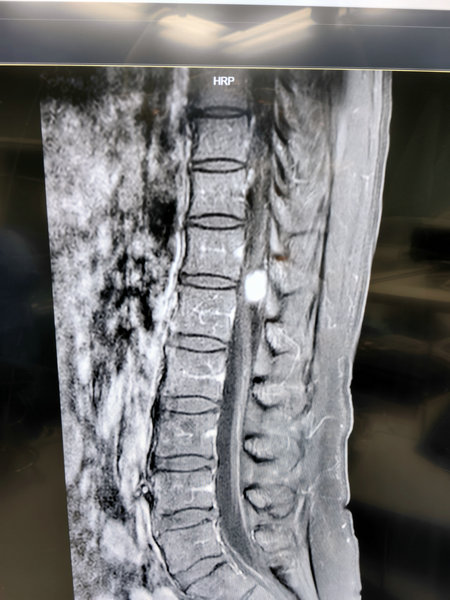

50岁的魏女士,半年前开始出现左下肢疼痛,本以为单纯的腰间盘突出,但右下肢也逐渐出现了疼痛,为查找病因、及时诊治,魏女士遂到齐医附属二院求治,经核磁共振检查,结果显示魏女士的胸12-腰1之间椎管内生长了肿瘤,于是魏女士的家属带着片子找到了齐医附属二院骨外三病区,刘艳楠副主任结合片子以及对患者进行专科检查后建议手术治疗,经过完善术前检查,手术顺利进行,术后恢复良好,魏女士双下肢疼痛症状消失,走路时两条腿也变得轻松了。

椎管内肿瘤的临床表现在疾病的初期阶段可能并不典型,与退行性疾病表现类似,仅表现为疼痛,或可以没有任何症状,但当出现肢体麻木或无力时,应当怀疑椎管内肿瘤的可能,及时行MR检查以明确诊断,除部分髓内肿瘤和硬膜外肿瘤为恶性外,大部分椎管内肿瘤均为良性肿瘤,虽然是一种良性肿瘤,但随着肿瘤的不断生长会逐渐造成脊髓和神经的压迫,导致受压平面以下的肢体运动、感觉、反射、括约肌功能以及皮肤营养出现障碍。早期手术效果明确,手术效果好,患者神经功能一般均可以得到明显的改善。